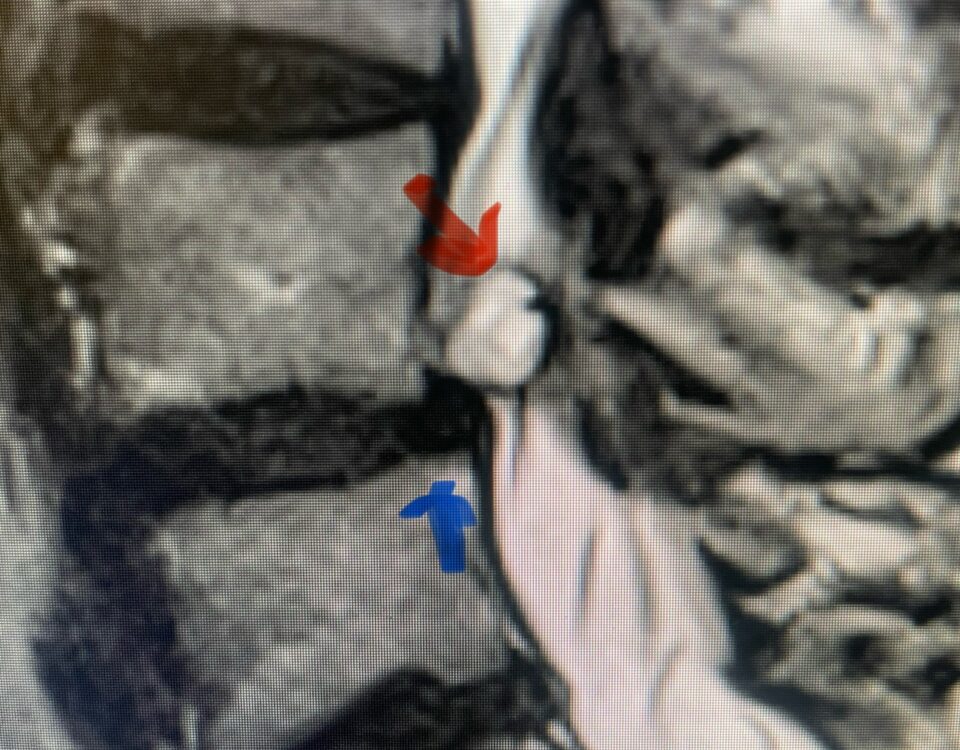

The actual structural cause of lumbar thecal sac compression can vary in degenerative spondylolisthesis and stenosis. The culprits are commonly thickened ligamentum flavum or severe facet […]

After 25 years in practice, I still find it challenging, but quite rewarding: removing degenerative material off the dural membrane in the lumbar spine. Some people […]